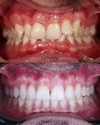

Zirkonyum uygulamalar

Porselen uygulamaları

Laminate veneer